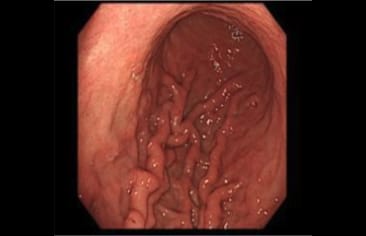

内視鏡検査とバリウム検査の比較

比べてみると内視鏡検査の方が画像が鮮明に見えることが分かります。

内視鏡検査

日本消化器内視鏡学会ホームページより